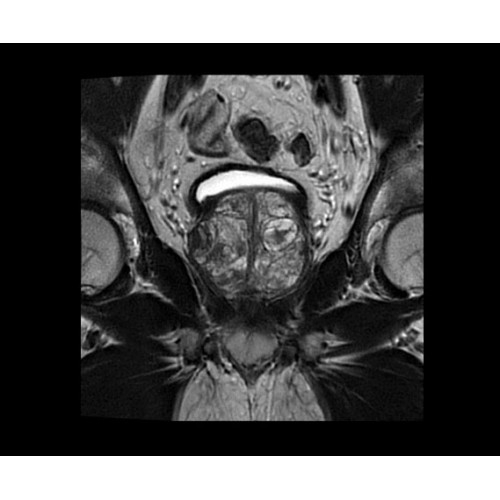

В систему SIGNA PET/MR встроены запатентованные детекторы кремниевого фотоумножителя (SiPM) и сверхчувствительные кристаллические сцинтилляторы на основе лютеция толщиной 25 мм. Благодаря этому обеспечивается исключительная чувствительность и возможность использования времяпролетной диагностики (TOF).

Кроме того, в результате использования технологии TOF и инновационной технологии реконструкции Q.Clear вы сможете добиться прекрасного соотношения сигнал/шум. А благодаря технологии нулевого времени эхо (ZTE) визуализировать костную структуру без ионизирующего излучения. Все эти разработки для улучшения качества сканирования и точности анализа помогут вам использовать весь потенциал ПЭТ/МРТ.

• МРТ с функцией нулевого времени эхо (ZTE) отличается точностью, возможностью персональных настроек и отсутствием ионизирующего излучения. Она приходит на смену традиционному исследованию на основе рентгеновского излучения. МРТ с функцией нулевого времени эхо (ZTE) на базе SIGNA ПЭТ/МРТ является более надежной и быстрой по сравнению с системами, использующими сверхмалое время эхо (UTE).